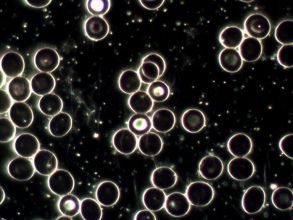

Levend Bloed Analyse

Levend bloed analyse is heel geschikt voor het herkennen van stofwisselings- en immuunsystemen. Door middel van het afnemen van een paar druppeltjes bloed via een vingerprikje, kunnen we heel veel aan jouw bloed aflezen. Er wordt gewerkt met een preparaat, waarin de witte en rode bloedcellen uren lang actief kunnen blijven. Vandaar dat er wordt gesproken van levend bloed.